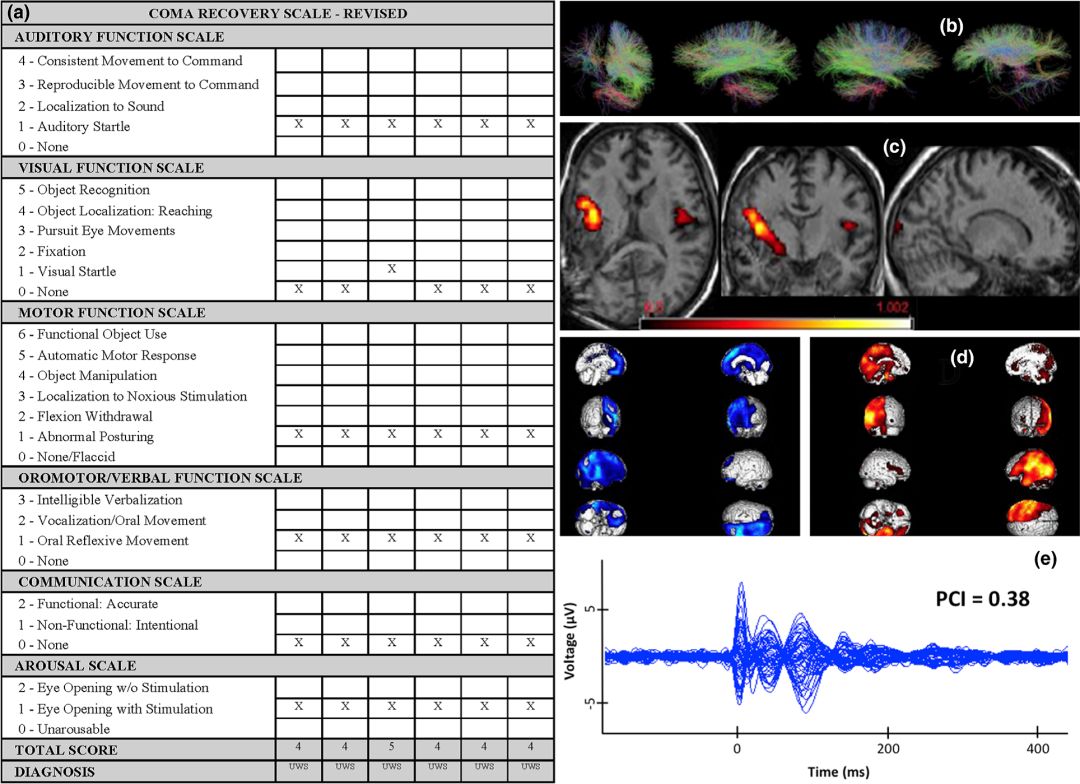

研究中选择24例入院时处于低意识状态的住院患者进行研究,莫达非尼通过经皮内窥镜胃造瘘管给药。剂量从每日100 mg逐渐增加至每日300 mg或最大耐受剂量,并采用最新的PDOC指南评估患者意识水平恢复情况,此外还采用了WHIM(行为观察评估工具)和昏迷恢复量表(修订版)。

研究发现,尽管遭受了严重的脑损伤并且意识改变状态持续了数月,但在24例患者中有11例观察到过度日间嗜睡改善。7例(29.16%)表现出认知改善,表现为对感觉刺激出现非反射性反应(从VS变为MCS)。24例患者中有4例恢复了完全意识:观察到这些患者功能性使用物体,并表现出一致的功能性互动交流。

莫达非尼治疗后的认知变化见表4。唤醒对意识很重要。莫达非尼可增强唤醒,这是意识的关键组成部分。它还能增加中缝背核的脑血流量,并激活脑干蓝斑核中的α和β肾上腺素能受体,这些受体弥散地投射到前脑和大脑皮层,在皮层激活中起着不可或缺的作用(即唤醒、注意力、执行功能和情绪)。